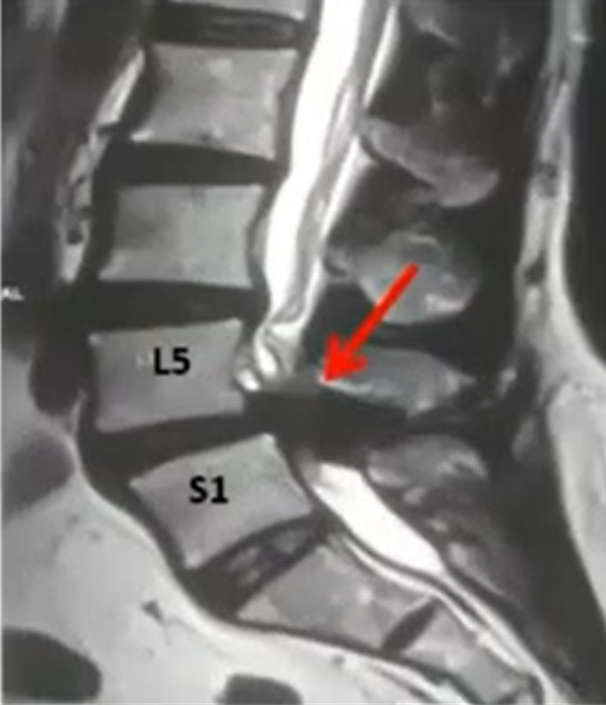

Spinal fusion is a surgical procedure that permanently joins two or more bones of the spine so they heal into one solid bone. This eliminates painful movement between them and stabilizes the spine.

The surgeon removes the damaged disc or diseased bone, places a cage or bone graft between the vertebrae, and secures it with screws and rods. Over months, the bones heal together naturally. The surgical approach (front, back, or side) depends on the patient's specific condition and body type.